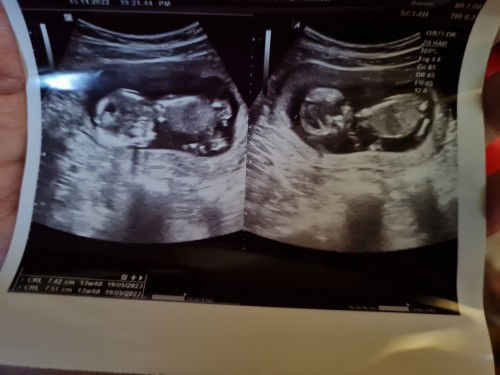

Baca usg caranya gimana ya bund??

Cara baca usg gimana ya bundaaa... soalnya dokternya kurang jelasin detail. Cuma bilang baik aja. Ada yg bisa bantu jelasin dari foto usg saya. #seriusnanya #bantusharing